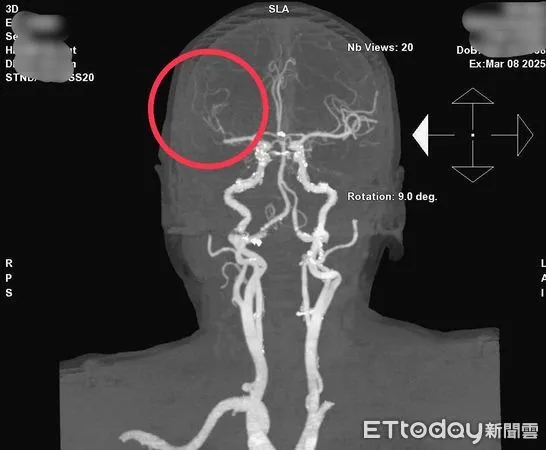

▲電腦斷層血管攝影檢查,紅圈處可見病人腦部血管阻塞。(圖/衛福部南投醫院提供,下同)

腦血管疾病長年嚴重威脅國人生命,高齡86歲婦人阿芬(化名)有心房顫動病史、平時可正常活動,家屬上周末發現她肢體無力、口齒不清的情況,送醫檢查顯示右側中大腦動脈梗塞性腦中風;經腦中風團隊評估後,立刻由三軍總醫院神經外科醫師陳奕安(現支援衛福部南投醫院)及心導管團隊執行「動脈內血栓移除治療」,成功搶回一命。